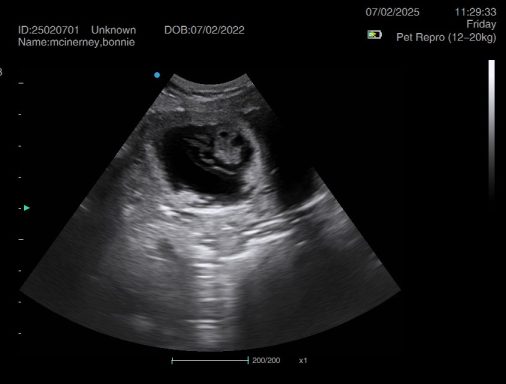

Ultrasound pregnancy scanning is a safe, non-invasive way to confirm pregnancy in dogs and cats, offering breeders and pet owners peace of mind and vital information to support responsible care. It allows us to detect gestational sacs, assess foetal development, and estimate litter size—all while ensuring the wellbeing of the animal.

Pregnancy can sometimes be detected as early as Day 18 post-mating, but scanning at this stage is not routinely recommended. Embryos are still developing and may not be clearly visible, and there is a natural risk of embryo resorption, which can lead to misleading or inconclusive results.

For the most accurate and reliable scan, we advise booking between Day 25 and Day 32, when pregnancy is more easily confirmed and foetal structures are clearer. If an early scan is performed and no pregnancy is detected, we offer a FREE complimentary re-scan after 7 days at the clinic to ensure clarity and support informed decision-making.

Our approach balances early insight with ethical care—always prioritizing the comfort of the animal and the accuracy of the results.